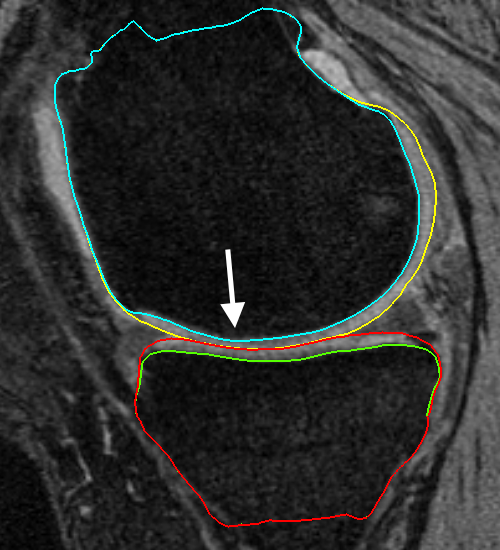

Fig. 3 qualitatively compares the segmentation accuracies between the two methods and the independent standard. Both the femur and tibia are shown with their respective bone and cartilage segmentations showing good agreement between learning-based segmentation and the independent standard.